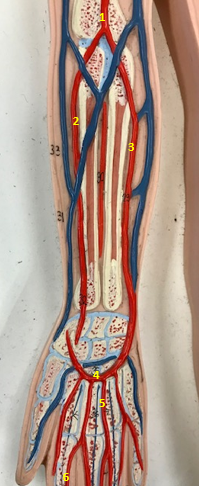

Right radial artery

Name #1

Supplies blood to hand wrist forearm

Function of right radial artery (1)

Right ulnar artery

Name #2

Supplies blood to fingers hand wrist forearm

Function of right ulnar artery (2)

Right brachial artery

Name #3

Supplies blood to arm forearm hand

Function of right brachial artery (3)

Right axillery artery

Name #4

Supplies blood to right armpit and upper limb

Function of right axillery artery (4)

Right brachial artery

Name #1

Right radial artery

Name #2

Right ulnar artery

Name #3